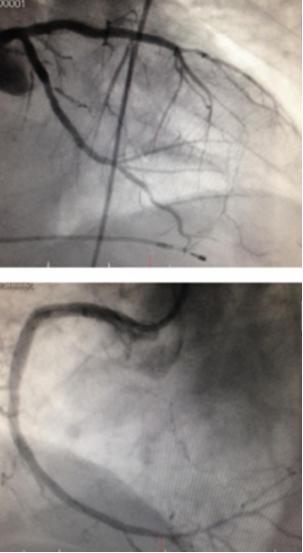

冠脉造影显示三支病变,前降支近段闭塞、回旋支近中段狭窄90%,右冠脉中段也有90%以上的弥漫狭窄。术中判断前降支为罪犯血管,优先进行支架植入处理,择期再处理右冠和回旋支病变。1周之后,患者三支血管均完成血运重建,术后服用阿司匹林、氯吡格雷、阿托伐他汀、卡托普利、卡维地洛,并进行心脏康复治疗。[1]

图2 冠脉造影结果

图3 冠脉PCI术后